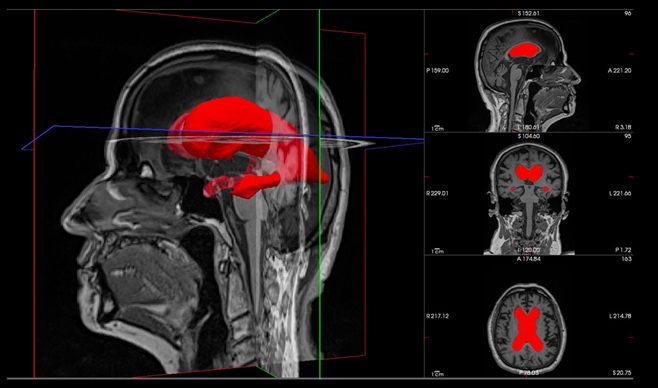

- Una revisión destaca los avances en una vía de atención de precisión para el manejo del meningioma